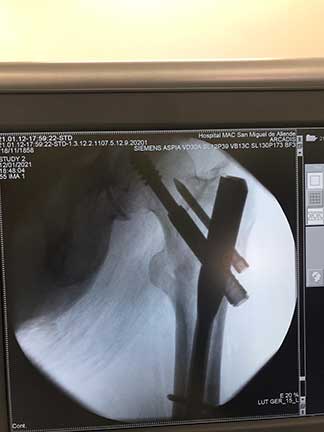

Artroscopia

de cadera

Cirugía mínima invasiva que se realiza haciendo tres puertos alrededor de la cadera por los cuales se introduce una cámara y observamos el interior de la articulación para buscar el daño o problema, también se introducen instrumentos con los cuales se permiten reparar las lesiones.

¿Por qué se realiza?

Está indicada en un paciente adulto joven para diagnosticar y tratar con certeza problemas de bloqueo en la cadera, extracción de cuerpos libres intrarticulares, rupturas de labrum, lesiones del cartílago y choque femoroacetabular.